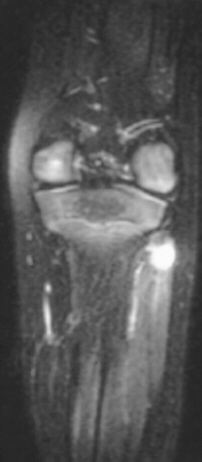

Radiographic examination of the left knee revealed no osseous abnormalities . A fullness of the soft tissues was evident over the fibular head. MRI examination of the left knee displayed a 2 cm. by 0.8 cm. lobulated mass in the region of the common peroneal nerve with no enhancement . On the T-2 weighted sequences there was abnormal increased signal of the tibialis anterior, extensor digitorum longus and peroneus longus muscle bellies suggesting atrophy . EMG/NCS were performed which clearly documented electrodiagnostic evidence of a severe peroneal neuropathy distal to the take-off of the nerve to the short head of the biceps.